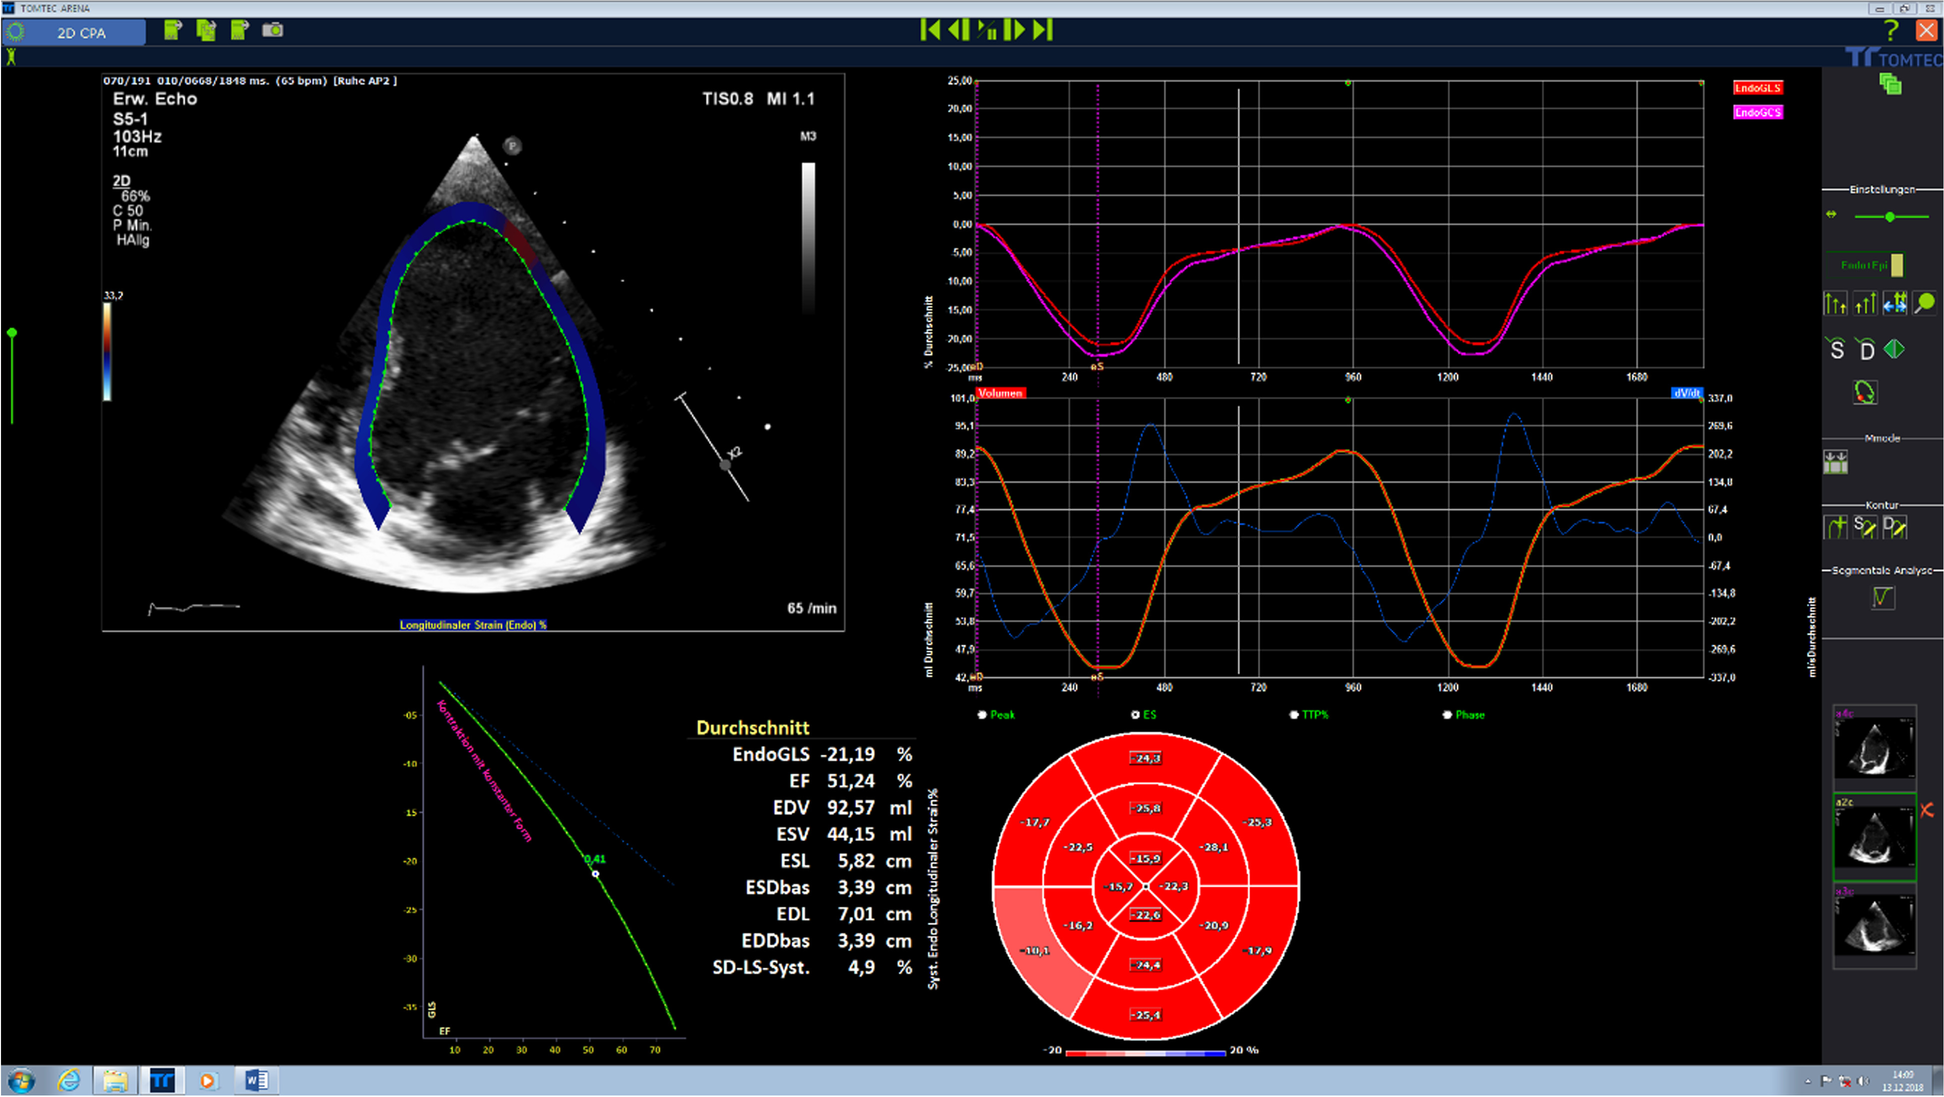

Strain imaging

Strain imaging is commonly used for the assessment of ventricular function allowing additional measurement of regional differences in contraction (dyssynergy) or dyssynchrony. Strain imaging (Fig. 1) measures either regional systolic deformation (strain) or the rate of regional deformation (strain rate). The methods used are either tissue Doppler or Speckle tracking echocardiography [3]. Strain imaging can be combined with stress echocardiography (preferably physical exercise) to increase diagnostic sensitivity for early detection of ventricular dysfunction, which might be an interesting diagnostic tool in patient cohorts susceptible for subclinical cardiac dysfunction like patients with congenital heart disease, childhood cancer survivors, or patients with hematologic disease such as thalassemia major [3, 4].

Fig. 1

2D strain imaging allows the assessment of global and regional function based on the determination of qualitative and quantitative parameters (longitudinal, radial, circumferential strain): vendor-independent analysis software tools (such as the Tomtec 2D-CPA analysis) visualize LV myocardium, strain curves, and summarize the results in “bull-eye” plots, generating a fast and comprehensive overview on cardiac function